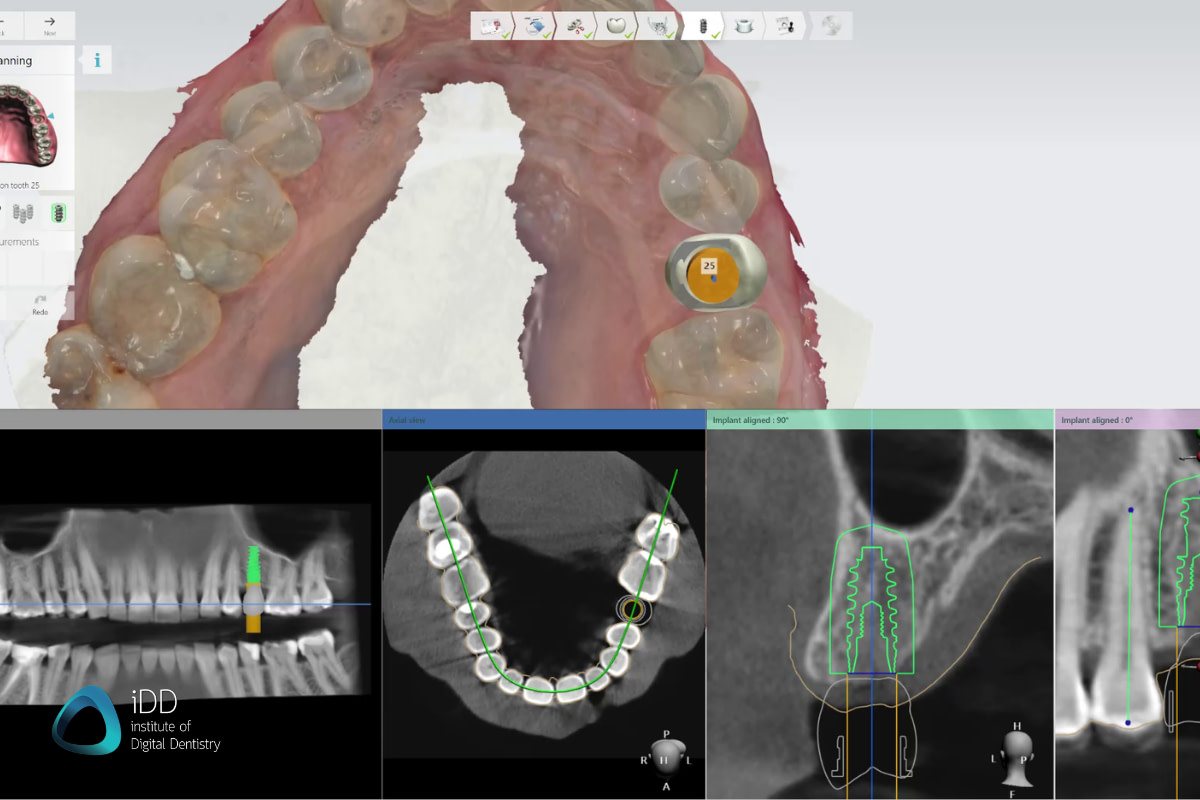

When designing the surgical guide itself - this is actually quite a straightforward task and shouldn’t take more than a couple of minutes.

You get to also design the size of your guide. For a single-unit case, it’s generally recommended to extend the guide over at least an entire quadrant, as you will achieve more stability from fitting the guide to more teeth. You can add cutouts to help you verify proper seating in the patient’s mouth or add the patient’s ID.

The design and digital library of the implant guide also accounts for a metal sleeve if required for your guide, that is purchased from the distributor and later inserted into your guide.

The surgical guide can be either created as a pilot guide - for use with the initial pilot drill only or fully guided - to assist you throughout the entire drill sequence. This depends on the surgical kit of your choice.

Once happy with your design, you can export the STL and the drilling protocol in PDF to refer to later.

The surgical guide design is very straightforward and fully customizable. In the step pictured above, the dental technician (Hugh Cho) is adding windows to help assess proper seating in the patient’s mouth.